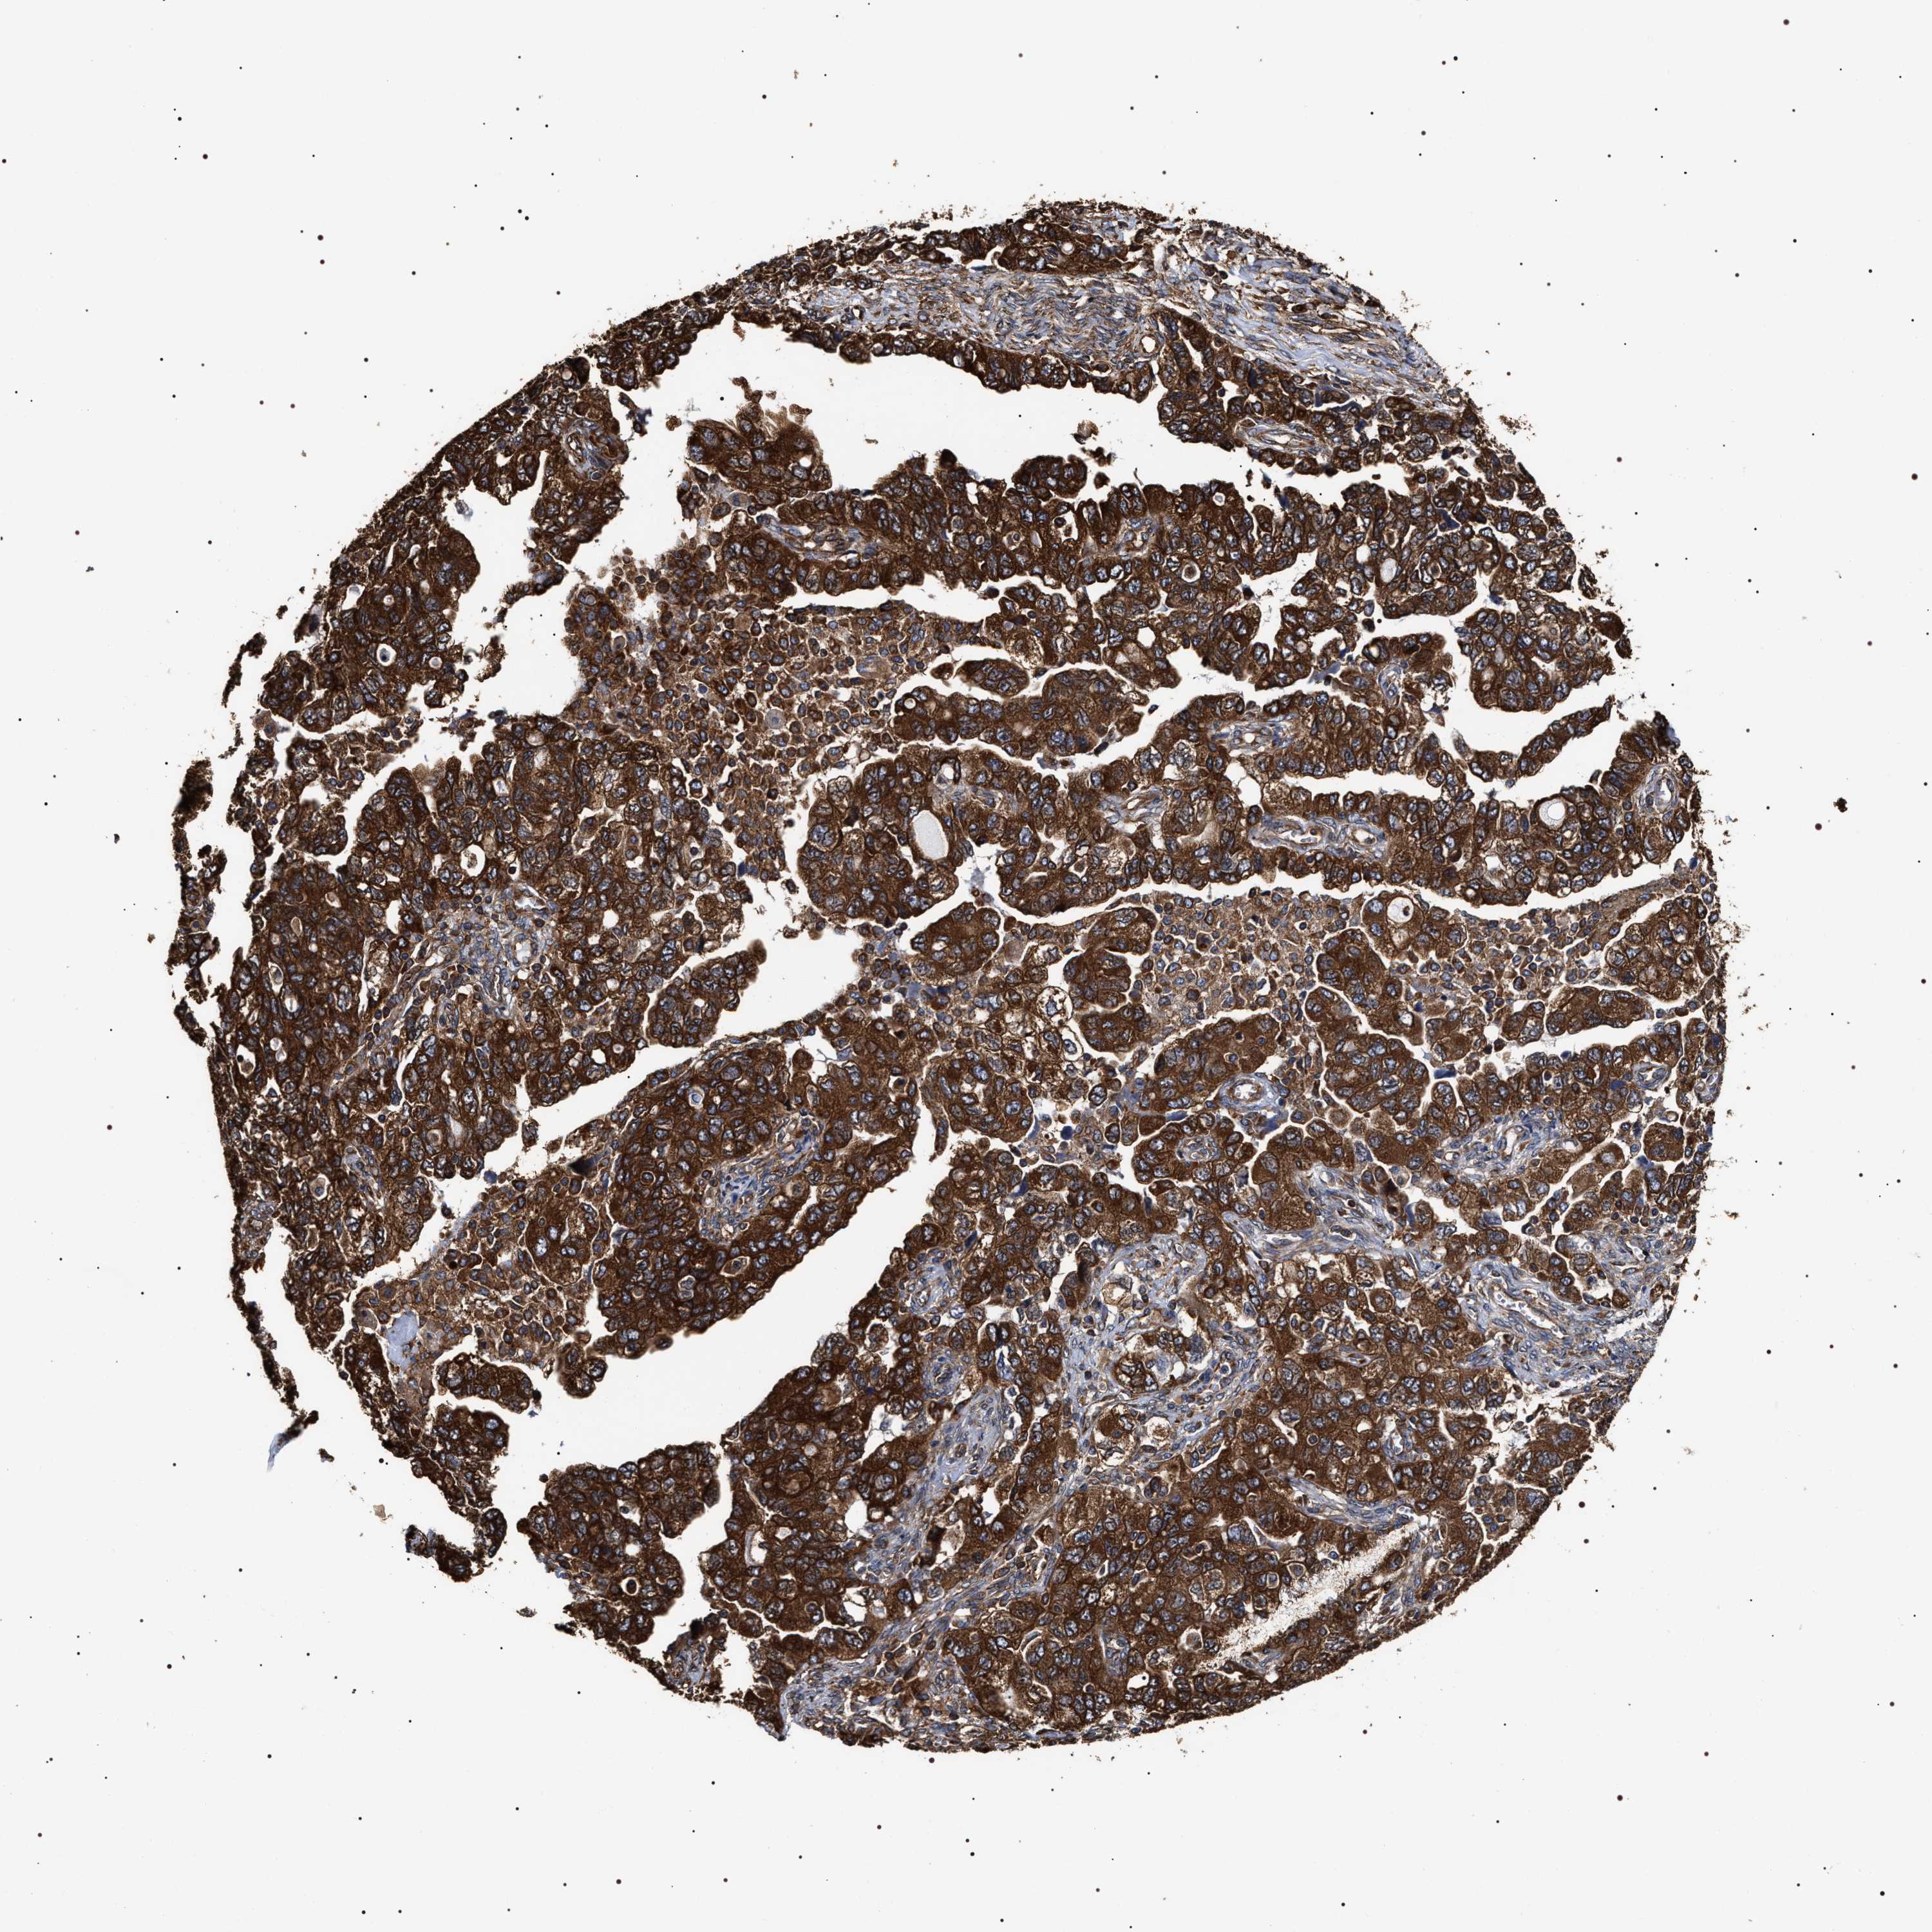

OVARIAN CANCER - Protein expressioni

A mouse-over function shows sample information and annotation data. Click on an image to view it in a full screen mode. Samples can be filtered based on level of antibody staining by selecting one or several of the following categories: high, medium, low and not detected. The assay and annotation is described here.

Note that samples used for immunohistochemistry by the Human Protein Atlas do not correspond to samples in the TCGA dataset.

Antibody stainingi

Antibody staining in the annotated cell types in the current human tissue is reported as not detected, low, medium, or high, based on conventional immunohistochemistry profiling in selected tissues. This score is based on the combination of the staining intensity and fraction of stained cells.

Each image is clickable and will lead to virtual microscopy that enables deeper exploration of all samples and also displays staining intensity scores, fraction scores and subcellular localization as well as patient and tissue information for each sample.

Antibody HPA020559

Antibody CAB026297

Cystadenocarcinoma, serous, NOS

Carcinoma, endometroid

Cystadenocarcinoma, mucinous, NOS

Carcinoma, NOS